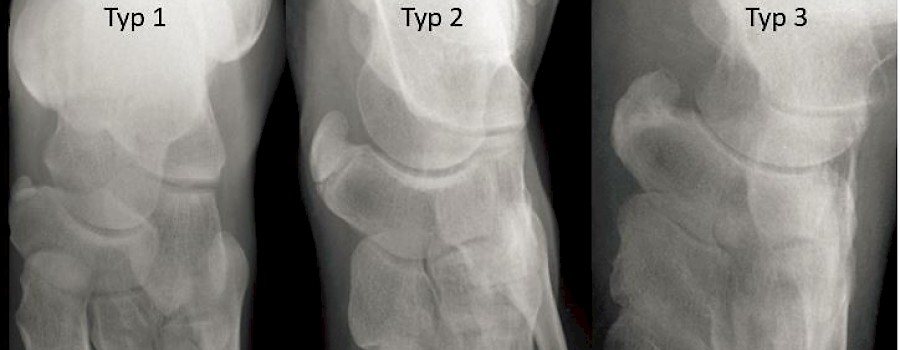

Die „Rosenberg-Aufnahme“ ist eine hilfreiche Alternative zur konventionellen Röntgendiagnostik bei der Kniegelenksarthrose. Die konventionelle radiologische Diagnostik bei der Gonarthrose beinhaltet Belastungsaufnahmen im Stand.